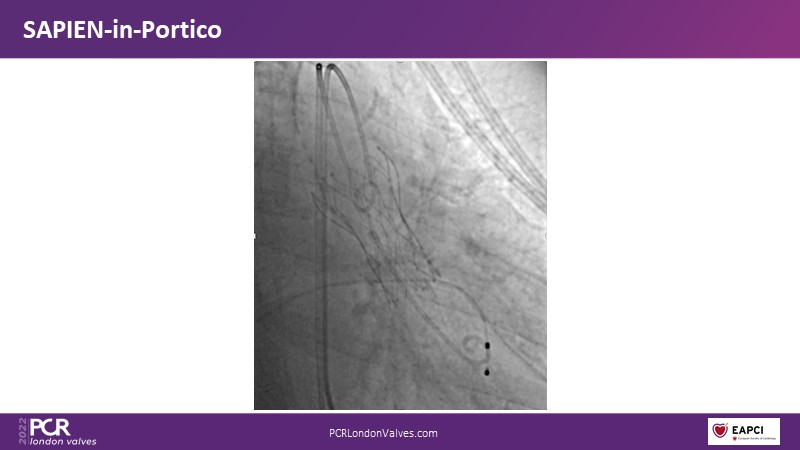

TAVI-in-TAVI - A road map for successful lifetime management

Join a team of experts that guide you through the basics of TAVI-in-TAVI, the procedural planning and techniques of implantation, followed by case examples with different index prostheses.